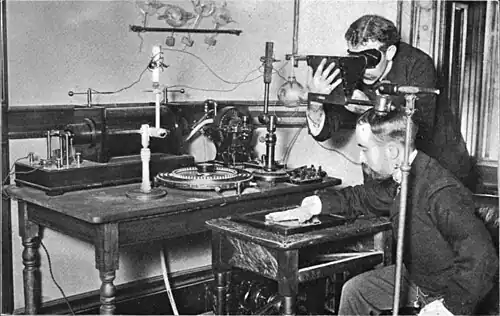

Radiography's origins and fluoroscopy's origins can both be traced to 8 November 1895, when German physics professor Wilhelm Conrad Röntgen discovered the X-ray and noted that, while it could pass through human tissue, it could not pass through bone or metal.[1] Röntgen referred to the radiation as "X", to indicate that it was an unknown type of radiation. He received the first Nobel Prize in Physics for his discovery.[2]

There are conflicting accounts of his discovery because Röntgen had his lab notes burned after his death, but this is a likely reconstruction by his biographers:[3][4] Röntgen was investigating cathode rays using a fluorescent screen painted with barium platinocyanide and a Crookes tube which he had wrapped in black cardboard to shield its fluorescent glow. He noticed a faint green glow from the screen, about 1 metre away. Röntgen realized some invisible rays coming from the tube were passing through the cardboard to make the screen glow: they were passing through an opaque object to affect the film behind it.[5]

Röntgen discovered X-rays' medical use when he made a picture of his wife's hand on a photographic plate formed due to X-rays. The photograph of his wife's hand was the first ever photograph of a human body part using X-rays. When she saw the picture, she said, "I have seen my death."[5]

The first use of X-rays under clinical conditions was by John Hall-Edwards in Birmingham, England, on 11 January 1896, when he radiographed a needle stuck in the hand of an associate. On 14 February 1896, Hall-Edwards also became the first to use X-rays in a surgical operation.[6]

The United States saw its first medical X-ray obtained using a discharge tube of Ivan Pulyui's design. In January 1896, on reading of Röntgen's discovery, Frank Austin of Dartmouth College tested all of the discharge tubes in the physics laboratory and found that only the Pulyui tube produced X-rays. This was a result of Pulyui's inclusion of an oblique "target" of mica, used for holding samples of fluorescent material, within the tube. On 3 February 1896 Gilman Frost, professor of medicine at the college, and his brother Edwin Frost, professor of physics, exposed the wrist of Eddie McCarthy, whom Gilman had treated some weeks earlier for a fracture, to the X-rays and collected the resulting image of the broken bone on gelatin photographic plates obtained from Howard Langill, a local photographer also interested in Röntgen's work.[7]

X-rays were put to diagnostic use very early; for example, Alan Archibald Campbell-Swinton opened a radiographic laboratory in the United Kingdom in 1896, before the dangers of ionizing radiation were discovered. Indeed, Marie Curie pushed for radiography to be used to treat wounded soldiers in World War I. Initially, many kinds of staff conducted radiography in hospitals, including physicists, photographers, physicians, nurses, and engineers. The medical speciality of radiology grew up over many years around the new technology. When new diagnostic tests were developed, it was natural for the radiographers to be trained in and to adopt this new technology. Radiographers now perform fluoroscopy, computed tomography, mammography, ultrasound, nuclear medicine and magnetic resonance imaging as well. Although a nonspecialist dictionary might define radiography quite narrowly as "taking X-ray images", this has long been only part of the work of "X-ray departments", radiographers, and radiologists. Initially, radiographs were known as roentgenograms,[8] while skiagrapher (from the Ancient Greek words for "shadow" and "writer") was used until about 1918 to mean radiographer. The Japanese term for the radiograph, rentogen (レントゲン), shares its etymology with the original English term.